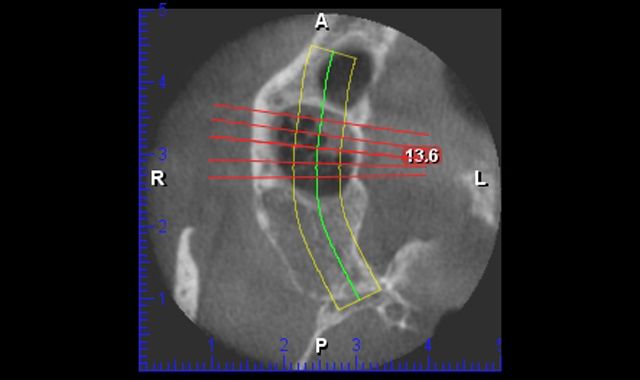

Having an intraoral scanner and a cone beam is the perfect marriage. Both are completely independent of each other. The scanner focuses on teeth and tissue and the cone beam addresses the bony architecture. When the STL files are joined in the lab, there is complete harmony. Like a great marriage, they make each other better. From my understanding and speaking with different vendors, one can take a DICOM file obtained from the CBCT, convert it, make a virtual model, 3D printed model and fabricate a crown. So, in theory, you could prep a tooth and have an edentulous area. Plan the implant and make the crown or partial all at the same time. And then there are times we just need to take an intraoral scan and make a crown inlay or onlay.